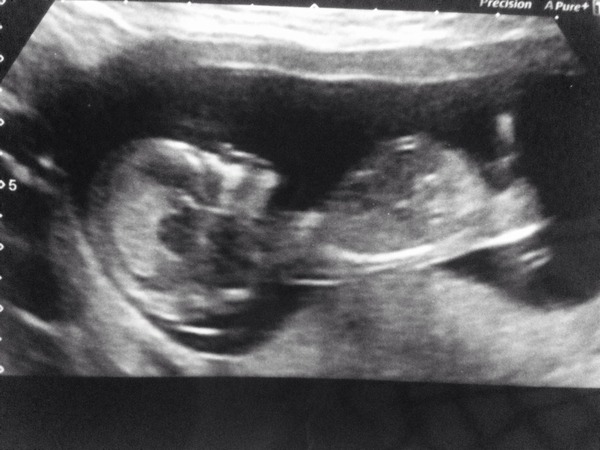

As for me, we had a scan to find out the sex of the baby today and we are having a little girl. Xmas Smile Very excited, although pretty surprised - I had convinced myself we were having a boy. Going to tell our families in a few days when we see them for Christmas.